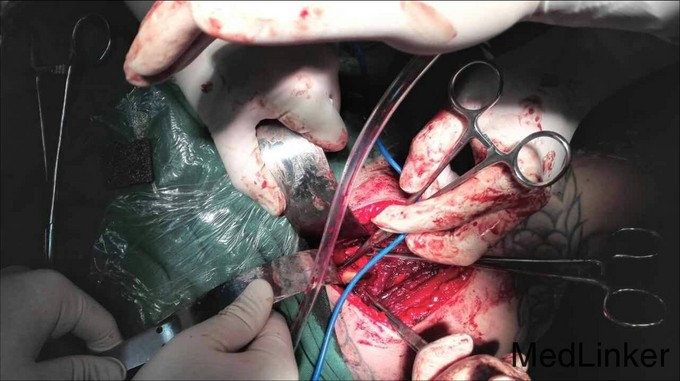

右侧臂丛神经阻滞麻醉 右肩关节前路切开复位螺钉内固定术 术后12日右上肢悬吊固定